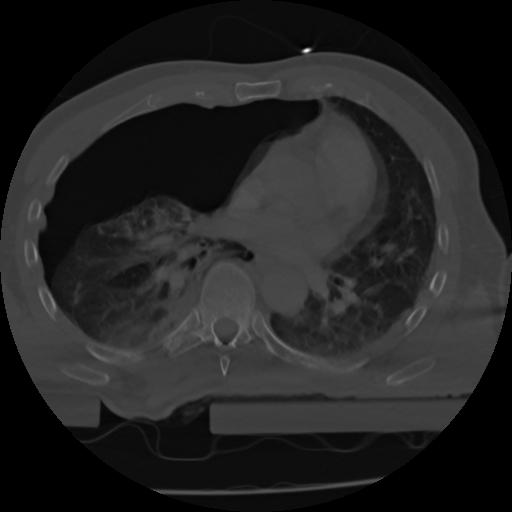

21 ANGIO,CE,Axial,3.0,ANGIO,,